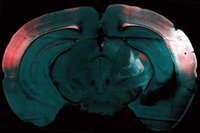

Headspace är ett dansverk om psykos/schizofreni och inspireras av forskningen inom området.